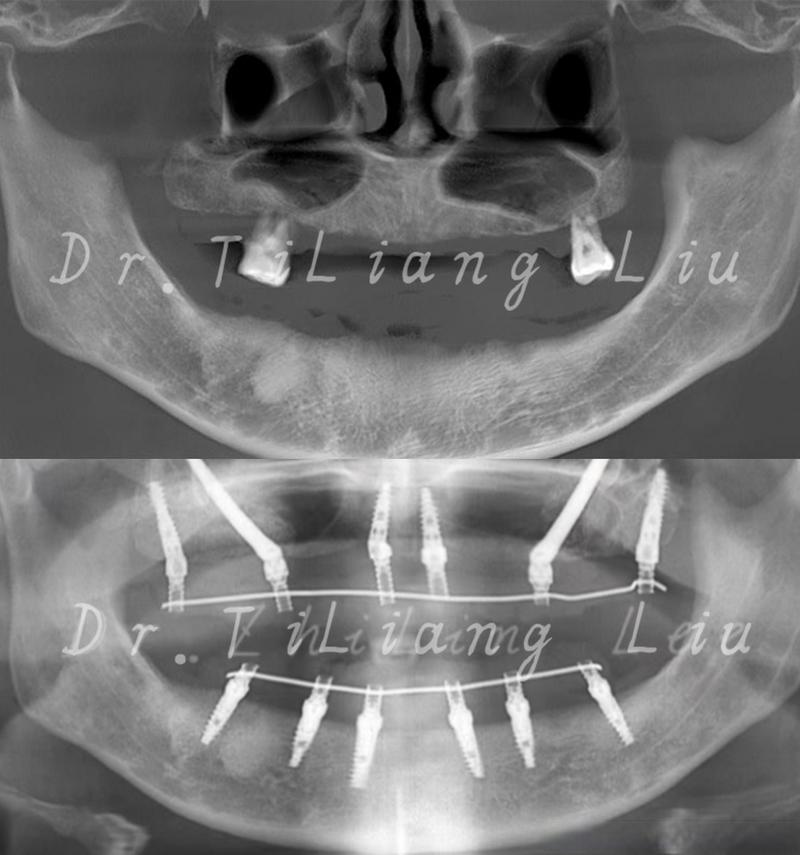

当你说“离上颌骨近”时,很可能是指缺牙位置距离上颌窦底壁非常近,甚至牙槽骨高度不足以安全植入种植体,这是种植牙中一个需要特别关注和处理的情况。

骨量不足: 上颌窦底壁下方是种植体需要扎根的牙槽骨,如果缺牙时间较长,牙槽骨会吸收变薄,当骨高度不足以完全包裹种植体(通常需要至少5-8mm高度,具体视种植体系统而定)时,直接种植就有风险:

- 种植体穿入上颌窦: 种植体尖端可能穿透上颌窦底壁,进入窦腔,这会导致感染、疼痛、种植体松动、失败等严重后果。

针对骨量不足靠近上颌窦的情况,种植牙医生通常不会直接种植,而是会采用以下上颌窦提升术来增加骨量,确保种植体安全植入:

上颌窦提升术(也叫上颌窦底增高术)

这是解决上颌窦区域骨量不足的标准方法,其原理是通过外科手术,将上颌窦底壁的骨膜和黏膜(称为“上颌窦粘膜”)向上推起,在窦底和推起的粘膜之间创造一个空间,然后填入骨移植材料,诱导新骨形成,从而增加骨高度。

- 适用情况: 骨量严重不足(通常剩余骨高度<4-5mm),或者需要同时提升较大范围。

- 手术过程: 在缺牙位置的牙槽嵴顶做一个小切口,翻开牙龈骨膜瓣,暴露上颌窦前外侧壁,在窦底开一个“窗”,小心地将上颌窦粘膜完整剥离并向上推起,将骨移植材料(自体骨、异体骨、人工骨或混合物)填入剥离出的空间,将骨膜瓣复位缝合。

- 特点: 视野清晰,提升高度大,但创伤相对较大,术后反应(肿胀、不适)可能稍重,通常需要4-6个月的骨愈合期,之后才能植入种植体(有时也可在提升时同期植入,称为“同期种植”,但要求条件更严格)。